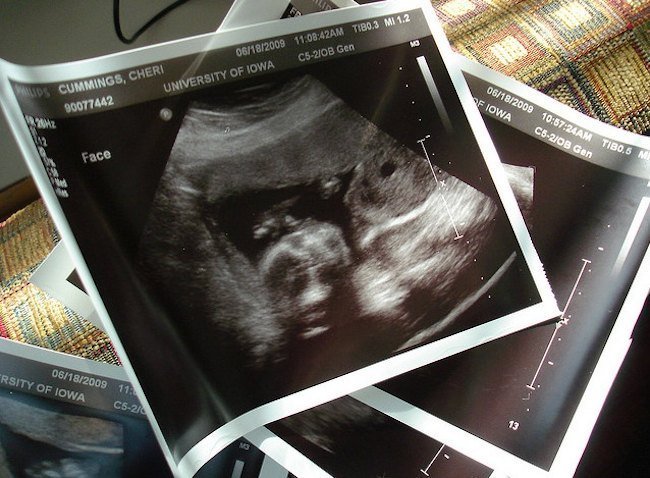

No suele ser habitual, al menos si nos fijamos en métodos más fiables que la tabla china para conocer el sexo del bebé, como las ecografías. Pero sí puede haber sorpresa al nacer, cuando las ecografías se equivocaron y el bebé es niño en vez de niña, o viceversa.

Me ha recordado este tema los comentarios a la tabla china, en una de las cuestiones que más interés suscita a los futuros papás, si será niño o niña. Y es que por mucho que se empeñen familiares o tablas en señalar que el bebé será de tal o cual sexo, lo cierto es que las ecografías no suelen engañar.

Aun así, y me remito a dos casos cercanos, a veces se equivocan. Los papás ya tienen todo dispuesto para una niña. Lo típico, ropita de nena, habitación con decoración adecuada a la “sensibilidad femenina” (tonos rosas y motivos de princesas…), el nombre que tanto costó escoger… y, ¡oh, sorpresa! ¡Pero si es un hermoso niño!

Que no se dejaba ver, que confundimos “la cosita” con el cordón, que no estaba muy desarrollado… en fin, que hasta que nació no se dieron cuenta de que era un varón. Al fin y al cabo, todos les hemos dado vueltas a las ecografías alguna vez intentando ubicar cualquier parte del cuerpo del bebé en una especie de cuadro abstracto…

Una amiga lo tuvo todo dispuesto para una niña, con las compras pertinentes antes de hora, hasta que en una de las últimas ecografías vieron que el bebé era niño… Menos mal que le dio tiempo a cambiar mucha de la ropita que había comprado.

No conozco el caso contrario, cuando los padres esperaban un niño y resultó ser niña, pero espero vuestros comentarios para saber si también se da esa situación. Imagino que, aunque menos frecuente (¿cómo se explican los “bultos” en esas partes?), también es posible.

Foto | Stephen Cummings en Flickr-CC